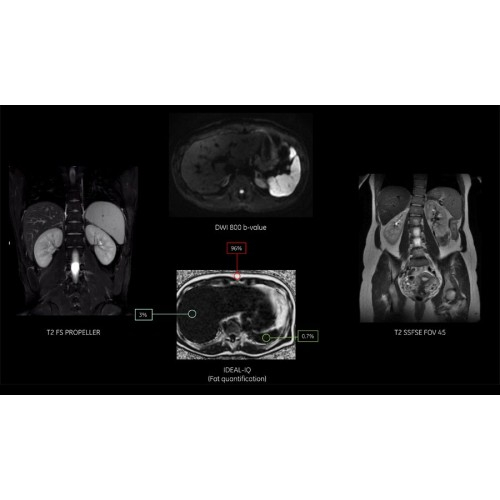

Технологии SIGNA Pioneer позволяют проводить полное исследование брюшной полости при свободном дыхании, минимизируя артефакты движения пациента, в том числе с МР-динамическим контрастированием.